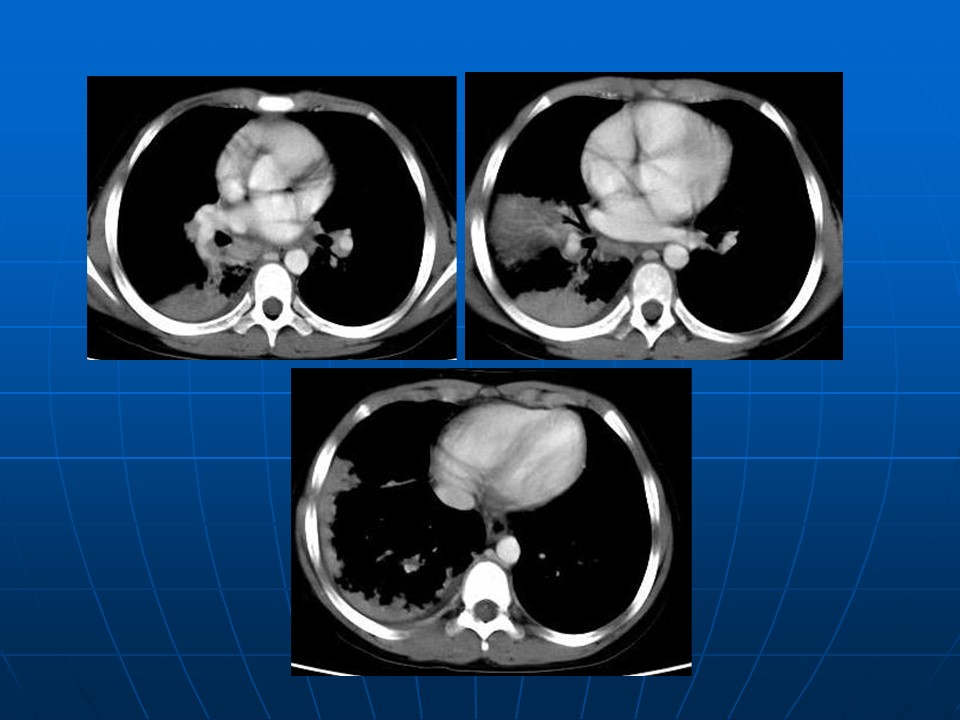

【PPT】肺部炎症新认识点滴